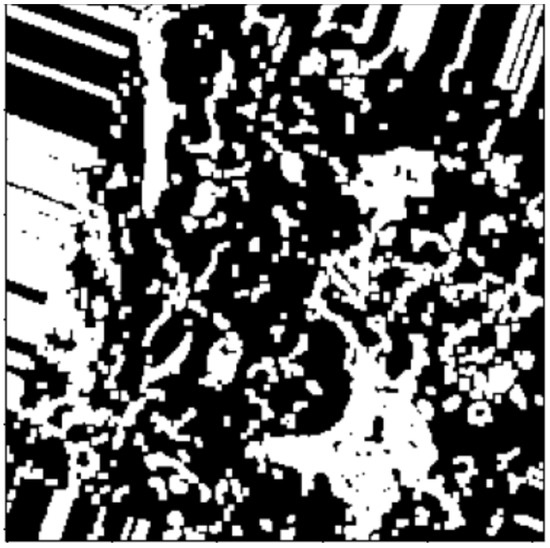

2.3.2. Watershed Segmentation

3. Results and Discussion